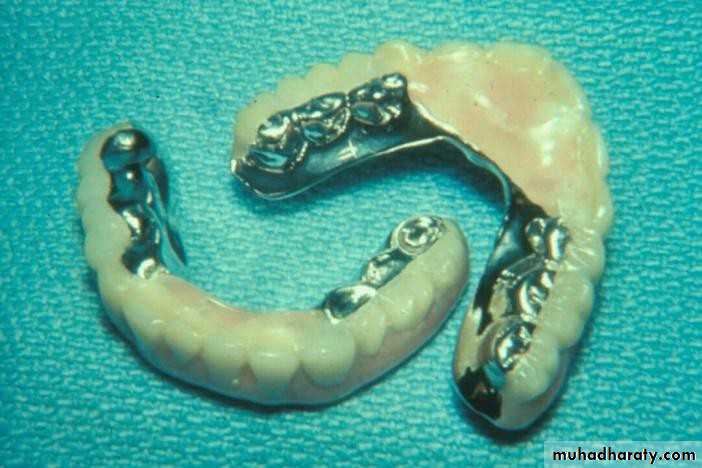

• Gold or metallic cast Copings and telescopic crowns are a method of improving overdenture retention. These

• may be conical crowns (semi- parallel wall) with a friction adaptation at the marginal area of the abutment, or Milled crowns for larger areas and parallel surfaces.

• Friction retention is more commonly used in exclusively tooth-supported overdentures

that are not supported by soft

tissue.